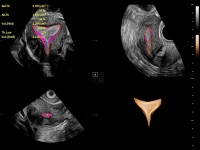

通過(guò)創(chuàng)新的Matrix E自適應(yīng)濾波算法,能有效濾除軟組織和噪聲信號(hào),最大限度保留超低速微細(xì)血流的信號(hào);結(jié)合超長(zhǎng)時(shí)間域算法,極大提升細(xì)微血流的敏感性和空間分辨率,更真實(shí)的反應(yīng)組織、包塊的血流灌注情況。